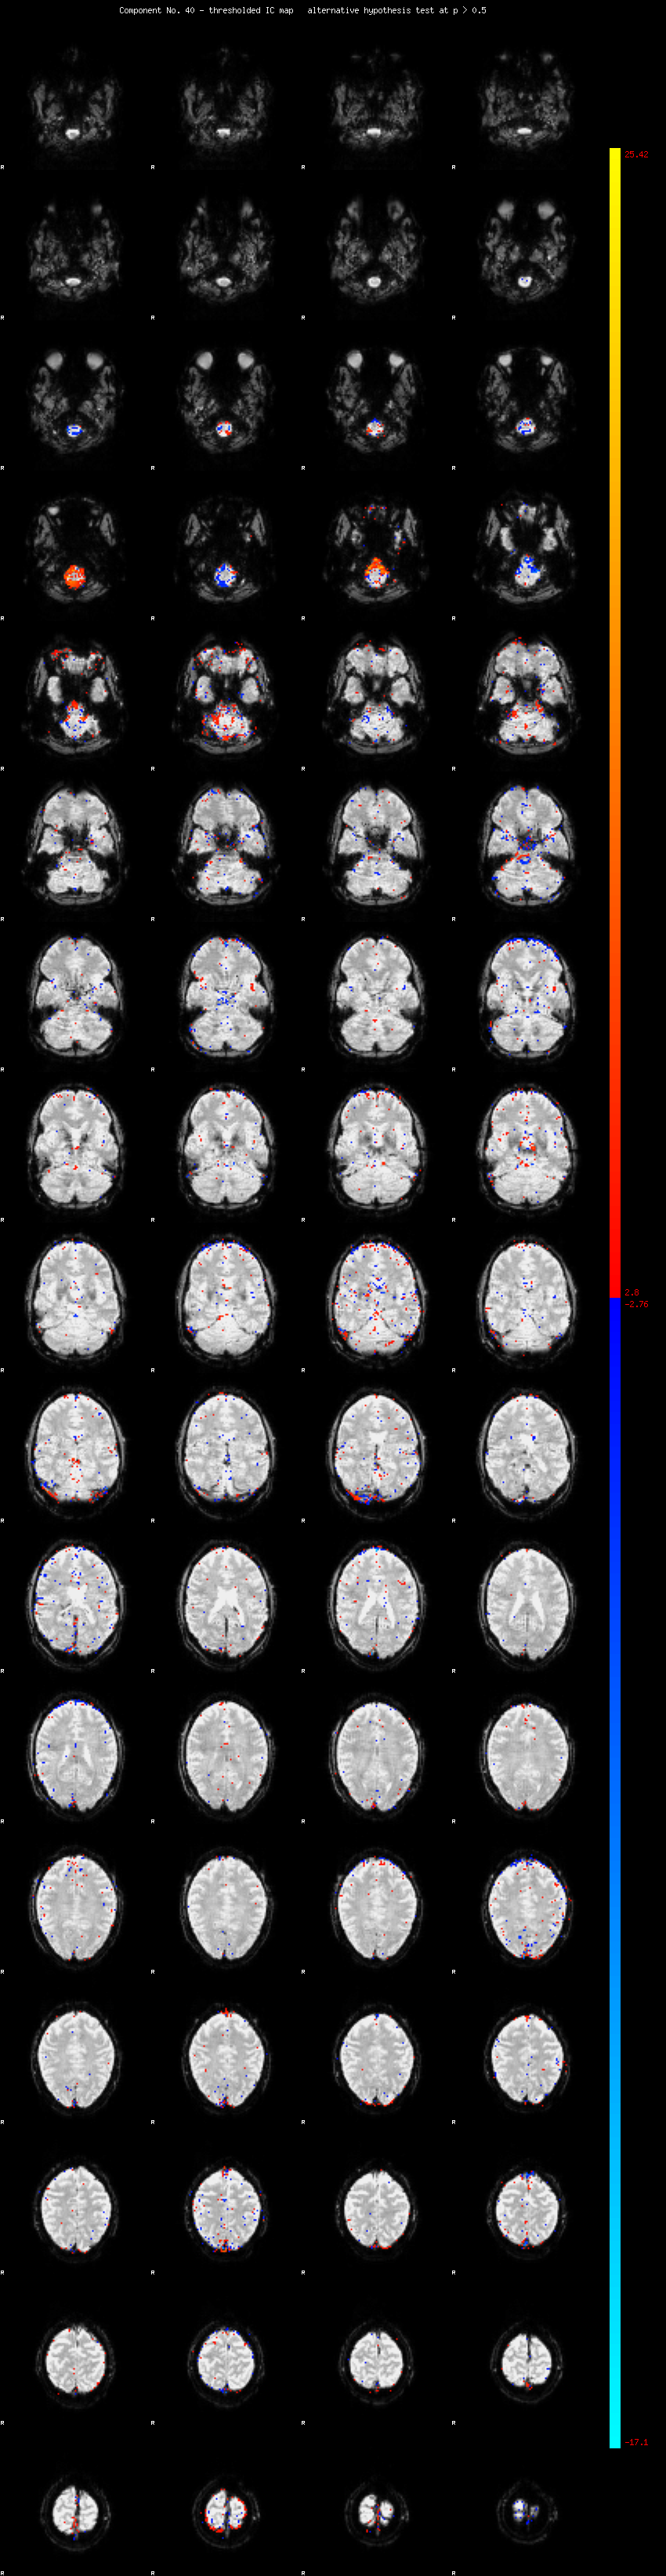

MELODIC Component 40

1.09 % of explained variance;     0.73 % of total variance

MMfit